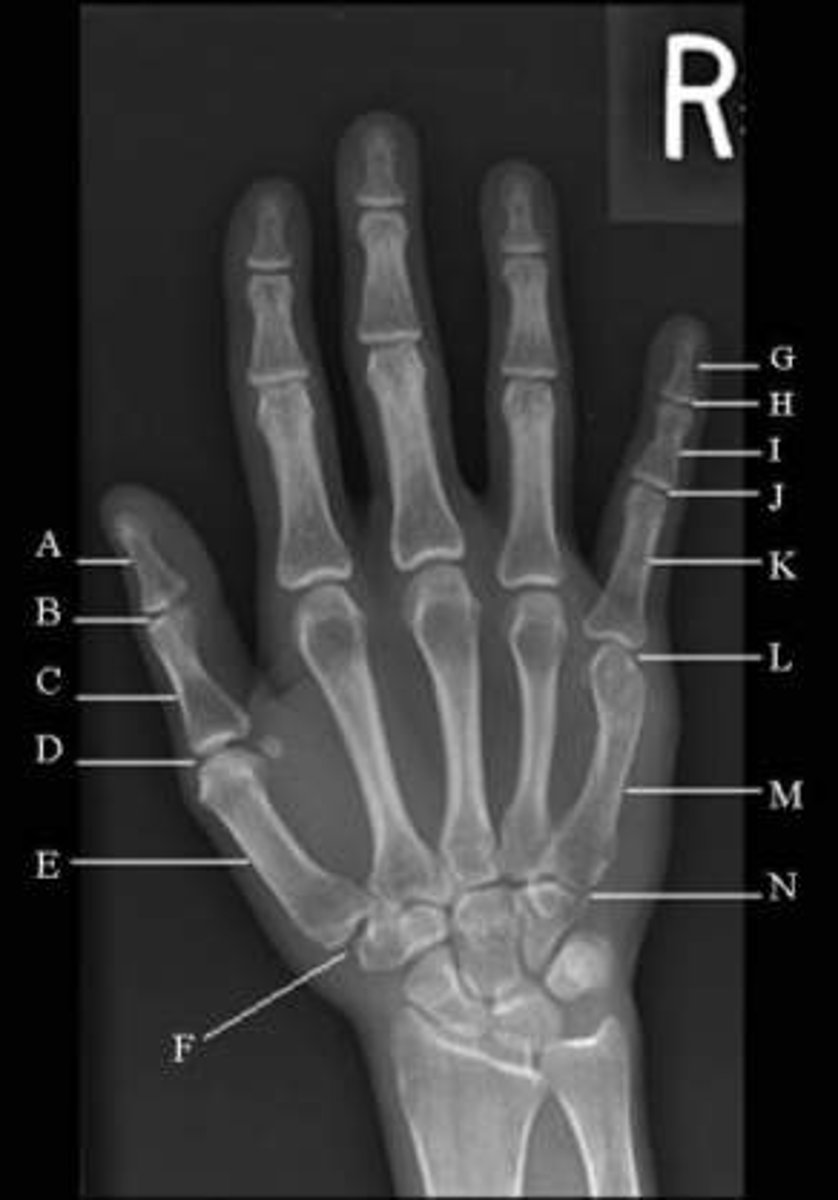

letter A

Lunate

letter B

Triquetrum

Letter C

pisiform

Letter D

Hamate

Letter E

Capitate

Letter F

Trapezoid

Letter G

Trapezium

Letter H

Scaphoid

Letter I

Metacarpals

Letter J

Proximal phalanges

Letter K

Middle phalange

Letter L

distal phalanges

letter M

radius

Letter N

ulna